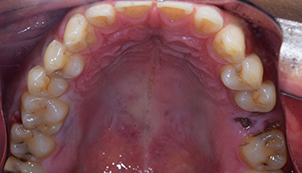

治療前:上の歯

担当医師所見:

臼歯部に残根状態の歯牙があり、またカリエス(虫歯)の散在が認められる。残根部分の両隣在歯は欠損部に対して傾斜し始めている。

治療前:下の歯

下顎右側臼歯部には一見大きな問題はないように見えるが、 頰側にフィステルと言われる排膿路があり発赤と主張があり炎症状態が続いていた。

治療前:前の歯

前歯部には離開部位があり、歯頚部にはカリエスが認められる。

治療後:上の歯

左上第1大臼歯は抜歯し、仮歯に置き換えた後治癒を待ちジルコニアBrで補綴。また右上第1大臼歯は根管治療終了後にジルコニアクラウンで補綴。前歯部は審美性を考慮しジルコニアボンドにて補綴した。 色調、形態共に調和がとれている。

治療後:下の歯

下顎右側第1大臼歯は抜歯後、仮歯に置き換え治癒を待った後ジルコニアステイニングBrにて補綴。 全顎的に色調・形態共に調和がとれている。

治療後:前の歯

前歯部はホワイトニング後に、仮歯に置き換え症状のないことを確認してからジルコニアボンドCrにて補綴。 審美性・機能面ともに調和がとれている。